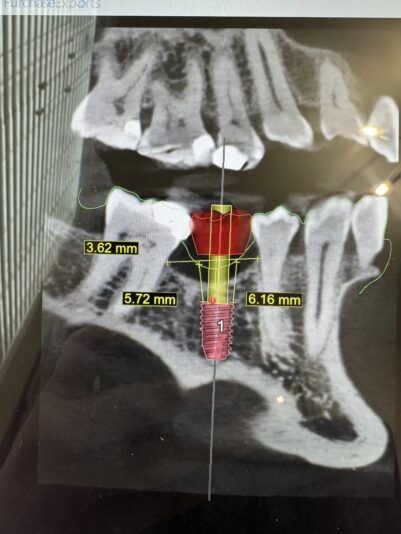

I’m planning for #30 implant (5×8.5mm virtually planned here). My concern is there is a vertical bone deficiency (about 3.62mm depression compared to the adjacent bone peaks) and that without vertical augmentation, the implant appears to be too submerged…which also appears to lead to a greater than ideal distance from the gingiva to the top of the implant platform from 5.7- 6.2mm (ideally I would like this distance to be 4mm…5mm at the maximum). I have not performed any vertical augmentation procedures but do have some knowledge of what to do if needed.